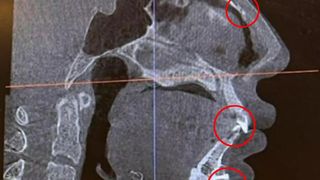

Controlul cu scanner din aeroprot ar fi semnalat prezența unui șurub chirurgical de 1 centimetru chiar sub buza de jos. Modelul crede că acel șurub a fost în corpul ei de când și-a pus o „proteză de bărbie”, în urmă cu opt ani.

„Am descoperit în mod neașteptat că am și unghii pe nas”, a mai exclamat modelul, șocată de ce a văzut că se află în corpul său.